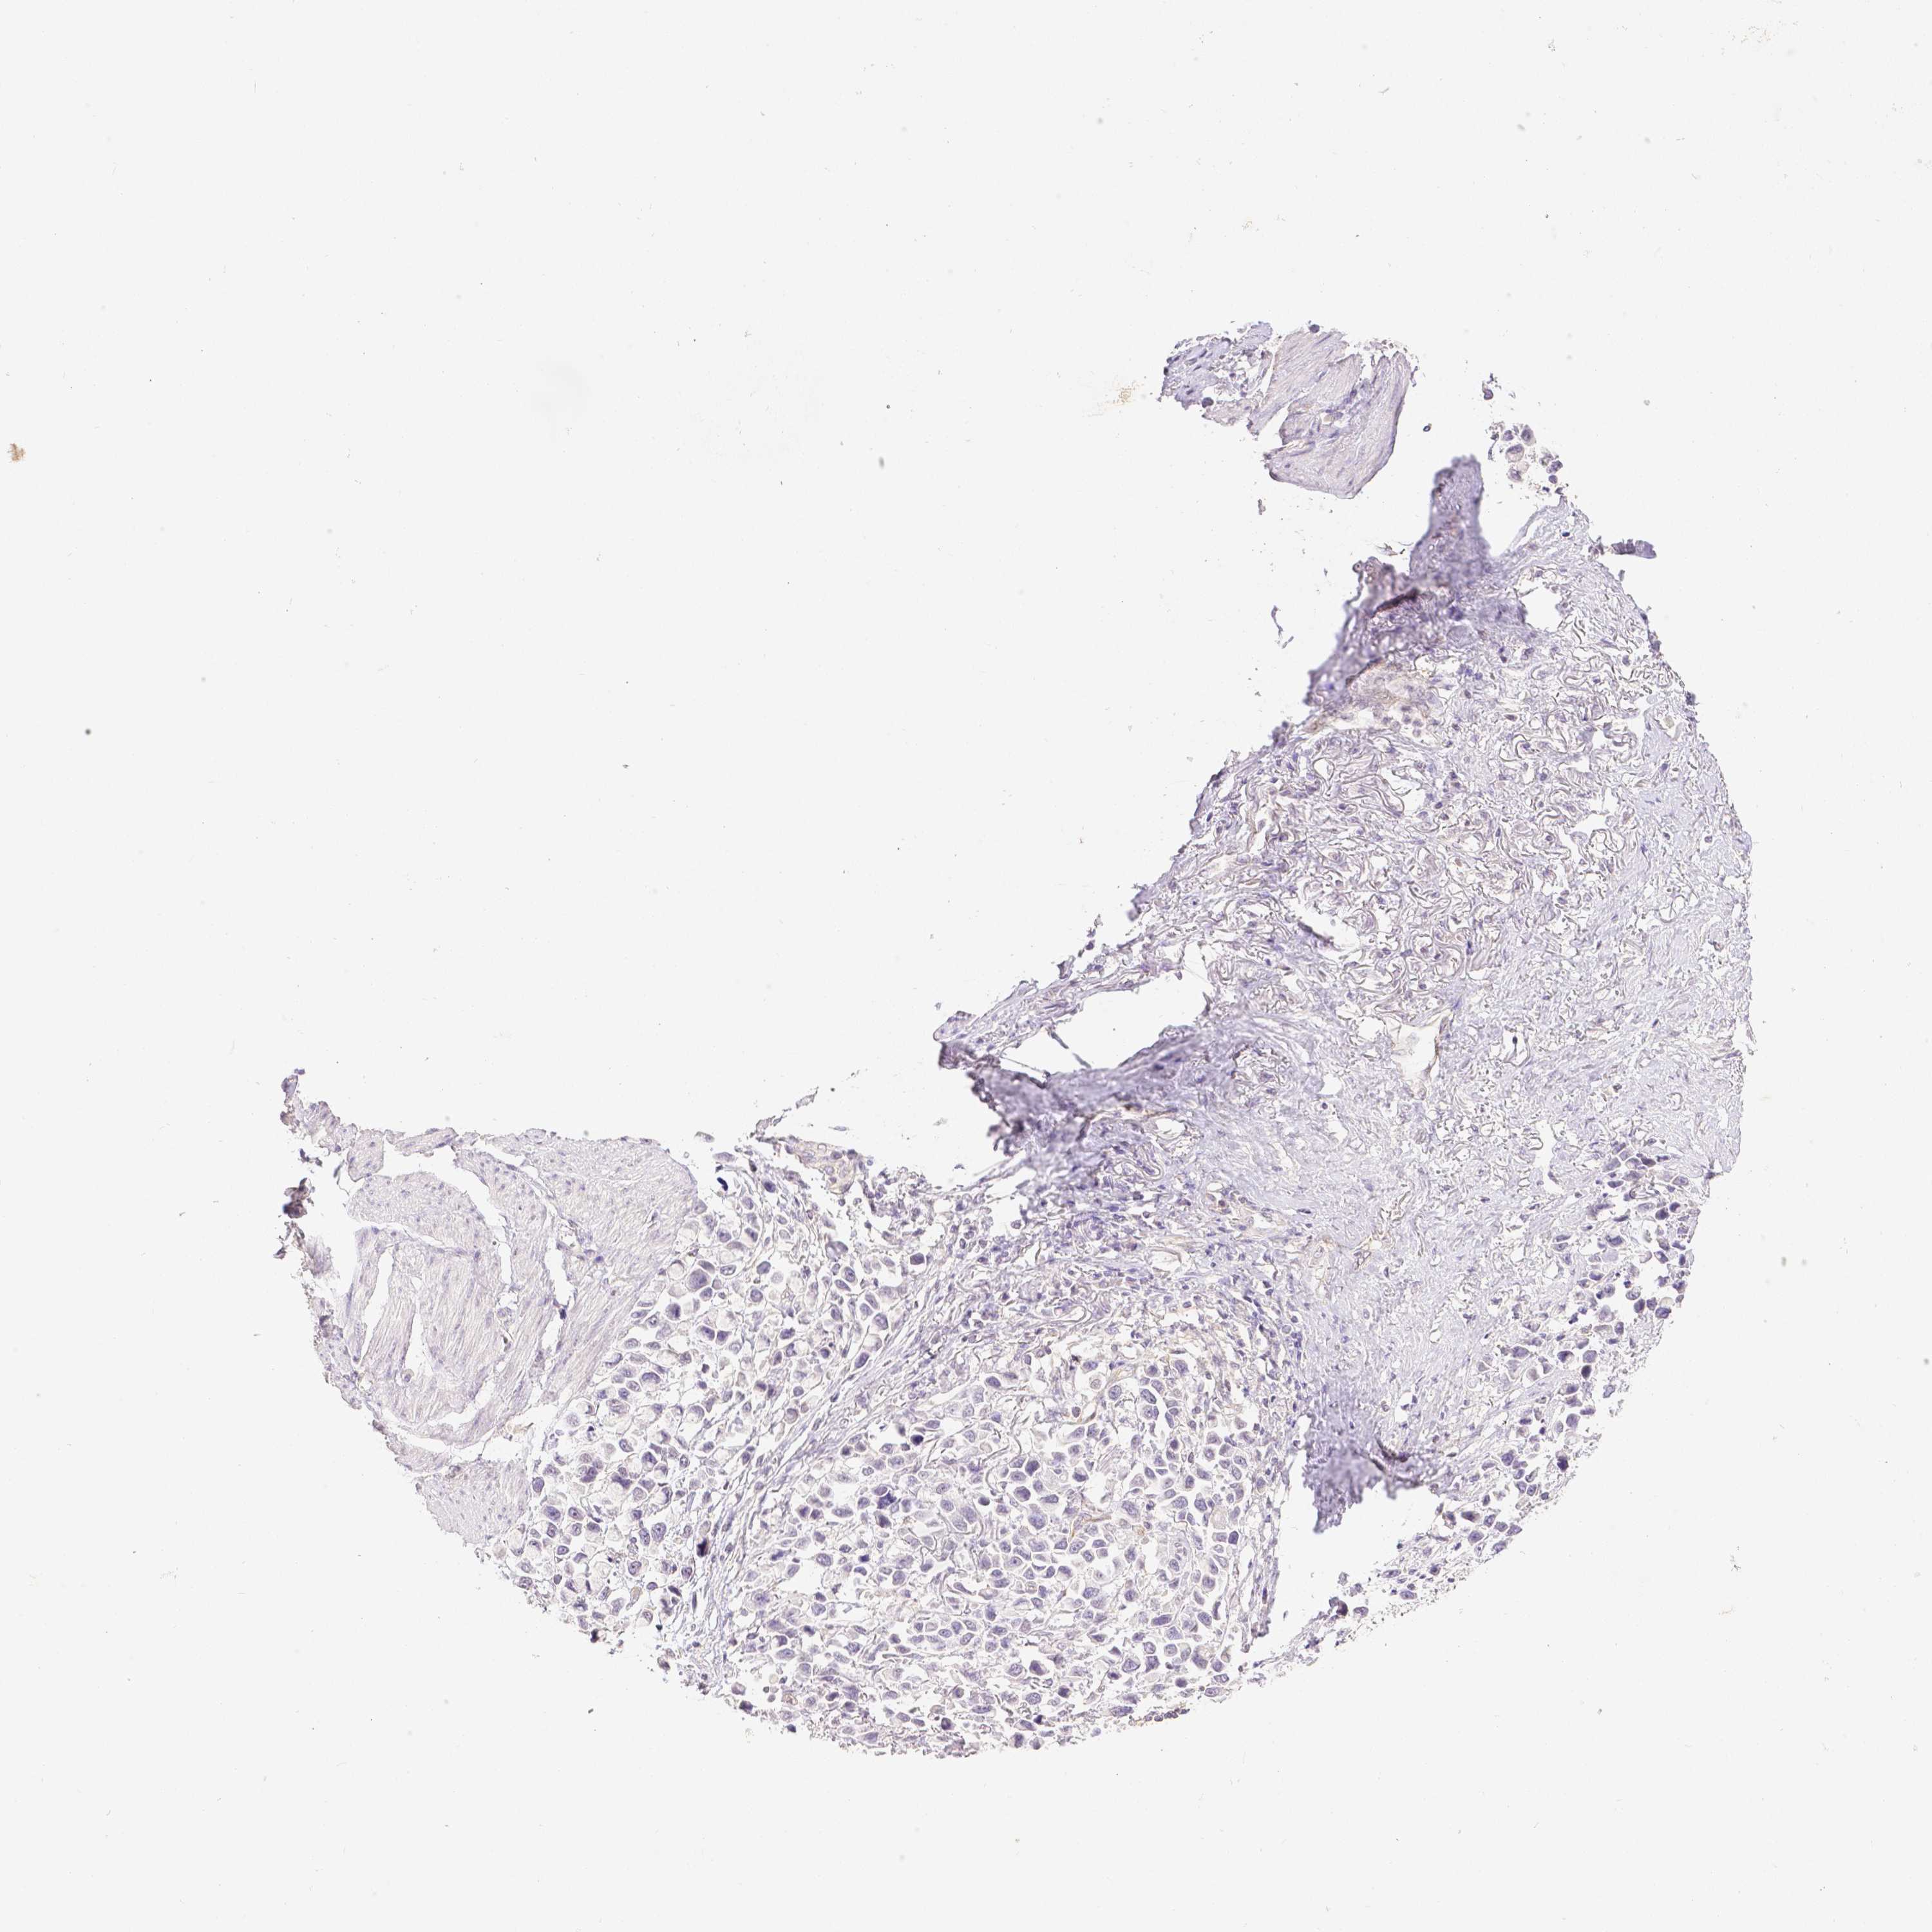

STOMACH CANCER - Protein expressioni

A mouse-over function shows sample information and annotation data. Click on an image to view it in a full screen mode. Samples can be filtered based on level of antibody staining by selecting one or several of the following categories: high, medium, low and not detected. The assay and annotation is described here.

Note that samples used for immunohistochemistry by the Human Protein Atlas do not correspond to samples in the TCGA dataset.

Antibody stainingi

Antibody staining in the annotated cell types in the current human tissue is reported as not detected, low, medium, or high, based on conventional immunohistochemistry profiling in selected tissues. This score is based on the combination of the staining intensity and fraction of stained cells.

Each image is clickable and will lead to virtual microscopy that enables deeper exploration of all samples and also displays staining intensity scores, fraction scores and subcellular localization as well as patient and tissue information for each sample.

Antibody HPA003733

Antibody CAB068243

Antibody CAB068244

Staining

High

Medium

Low

Not detected

Intensity

Strong

Moderate

Weak

Negative

Quantity

>75%

75%-25%

<25%

None

Location

Nuclear

Cytoplasmic/membranous

Cytoplasmic/membranous,nuclear

Adenocarcinoma, NOS